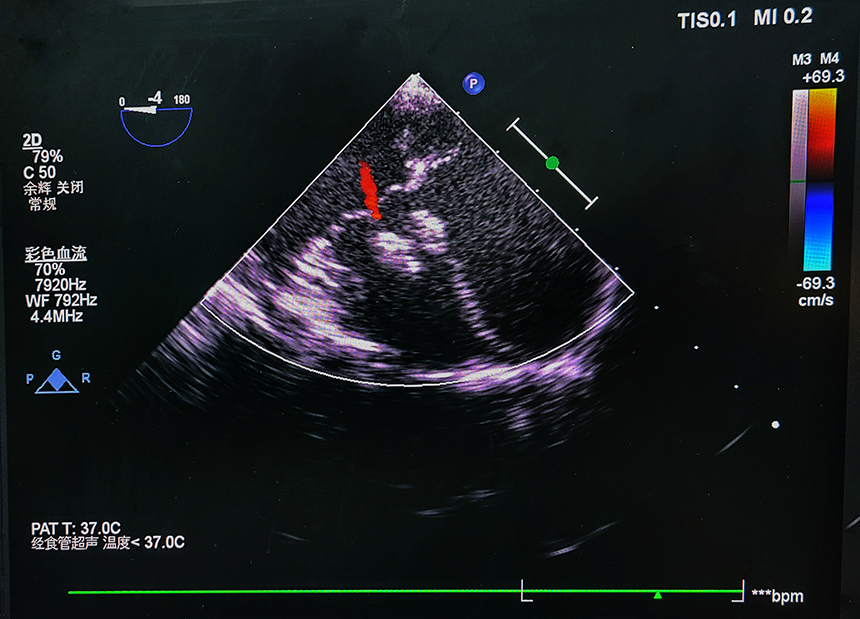

图4 可降解封堵器植入后

2021年12月9日上午11:00,手术准时开始。广西中医药大学附属医院胸心血管外科范悦主任、莫春镕医师、蒙裕国医师通过经食道超声详细评估,确定孩子心脏内有4mm大小的室间隔缺损。该病症符合介入治疗的要求,医疗团队熟练地在食道超声引导下,将“自膨式可降解室间隔缺损封堵器”由输送装置通路推送,并在心腔内成功展开和释放,完美地封堵住患者的室间隔缺损,手术顺利完成。上午11时45分,孩子顺利送回胸心血管外科病房,生命体征平稳。

范悦教授介绍,室间隔缺损(VSD)为临床上最常见的先天性心脏畸形,由于其特殊的解剖位置关系与血流动力学影响,以往此类介入手术通常采用的是传统金属封堵器,可能存在金属永久植入物的相关风险,特别是对心脏瓣膜和心脏传导系统的影响。而使用“可降解封堵器”不仅可以有效阻断异常通道,还可以避免金属永久性封堵器可能带来的远期并发症。可降解封堵器作为桥梁,仅作为临时的植入物,最终会分解成无毒的小分子水和二氧化碳被排除体外。原缺损部位上的封堵器网体表面会由患者的自身组织再生修复,并完全被覆盖。可降解封堵器在达到修复心脏缺损的同时又未在心脏内留下金属植入物,这项创新使瓣膜返流和心脏传导阻滞的风险大大降低。从手术操作流程看,可降解室间隔缺损封堵装置与常规金属封堵器类似,在心脏超声引导下,可有效观察到封堵器的位置及形态,具有较好的手术安全性。